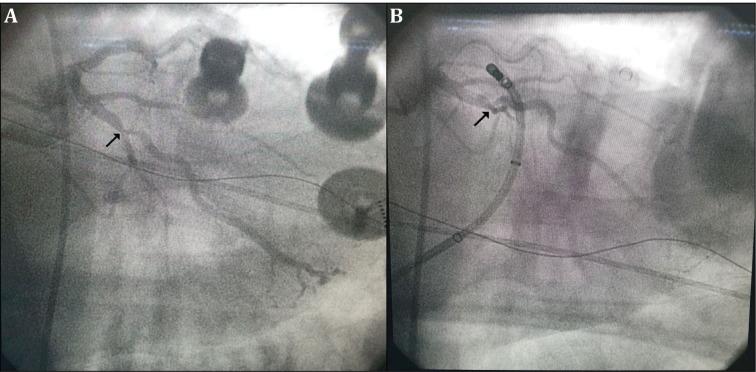

The left ventricular (LV) summit is the usual source of epicardial idiopathic premature ventricular contractions (PVCs). A 56-year-old male patient presented to the cardiology outpatient clinic with palpitations and dyspnea. Twelve-lead electrocardiography performed on admission revealed monomorphic PVCs with precordial QRS transition in the V1 derivation and an rS pattern in the D1 derivation and inferior axis. An electrophysiology study and ablation procedure were planned. Activation mapping guided by a three-dimensional electroanatomic system was conducted to identify the earliest site of ventricular activation of the PVCs. During the PVCs, the earliest ventricular activation was observed within the great cardiac vein (GCV) and preceded the QRS onset by 37 ms. Coronary angiography was performed before ablation in the coronary venous system (CVS) to assess the distance from the coronary artery, which showed severe stenosis in the left circumflex artery. Then, percutaneous coronary intervention was performed to address the left circumflex artery stenosis. Anatomic catheter ablation was performed in the aortic cusp and endocardial LV outflow tract, the sites adjacent to the LV-summit PVC origin. However, successful ablation could not be achieved. Subsequently, an irrigated radiofrequency current was delivered in the GCV for 60 seconds, with the power being gradually increased to 30 W and with an irrigation flow rate of 30 mL/min. After ablation, under isoproterenol infusion and burst pacing from the right ventricle, no PVC or ventricular tachycardia was observed. Special precautions should be taken to avoid coronary artery damage during ablation from distal CVS. This approach may increase the success of ablation and avoid potential complications.

左心室(LV)峰是心外膜特发性室性早搏(PVCs)的常见起源部位。一名56岁男性患者因心悸和呼吸困难就诊于心脏病门诊。入院时进行的12导联心电图显示单形性PVCs,胸前导联QRS波在V1导联移行,D1导联呈rS型且电轴下偏。计划进行电生理研究和消融手术。采用三维电解剖系统引导下的激动标测来确定PVCs最早的心室激动部位。在PVCs发作期间,最早的心室激动出现在大心脏静脉(GCV)内,比QRS波起始提前37毫秒。在冠状动脉静脉系统(CVS)进行消融术前进行冠状动脉造影,以评估与冠状动脉的距离,结果显示左旋支动脉严重狭窄。随后,进行经皮冠状动脉介入治疗以处理左旋支动脉狭窄。在主动脉瓣尖和左心室流出道内膜进行解剖性导管消融,这些部位与LV峰PVC起源相邻。然而,未能成功消融。随后,在GCV内输送灌注射频电流60秒,功率逐渐增加至30W,灌注流速为30mL/min。消融后,在静脉滴注异丙肾上腺素和右心室猝发起搏时,未观察到PVC或室性心动过速。在从远端CVS进行消融时,应特别注意避免冠状动脉损伤。这种方法可能会提高消融成功率并避免潜在并发症。